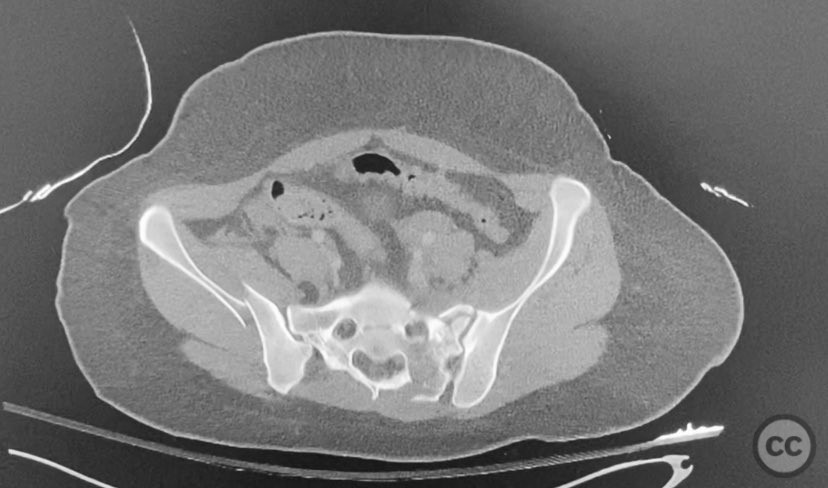

Clinical and radiological findings:  The patient presented following trauma with an unusual, significantly displaced right iliac fracture, accompanied by left-sided sacral and parasymphyseal ramus fractures. Initial AP pelvic radiography demonstrated the complex injury pattern. CT imaging provided detailed characterization of the iliac and sacral fractures, including assessment of displacement, bone quality, soft tissue status, and overall body habitus. No neurovascular compromise was reported. AO/OTA classification: Right iliac fracture 61B2.3 (partial unstable, lateral compression injury), left sacral fracture Denis zone I, left parasymphyseal ramus fracture.